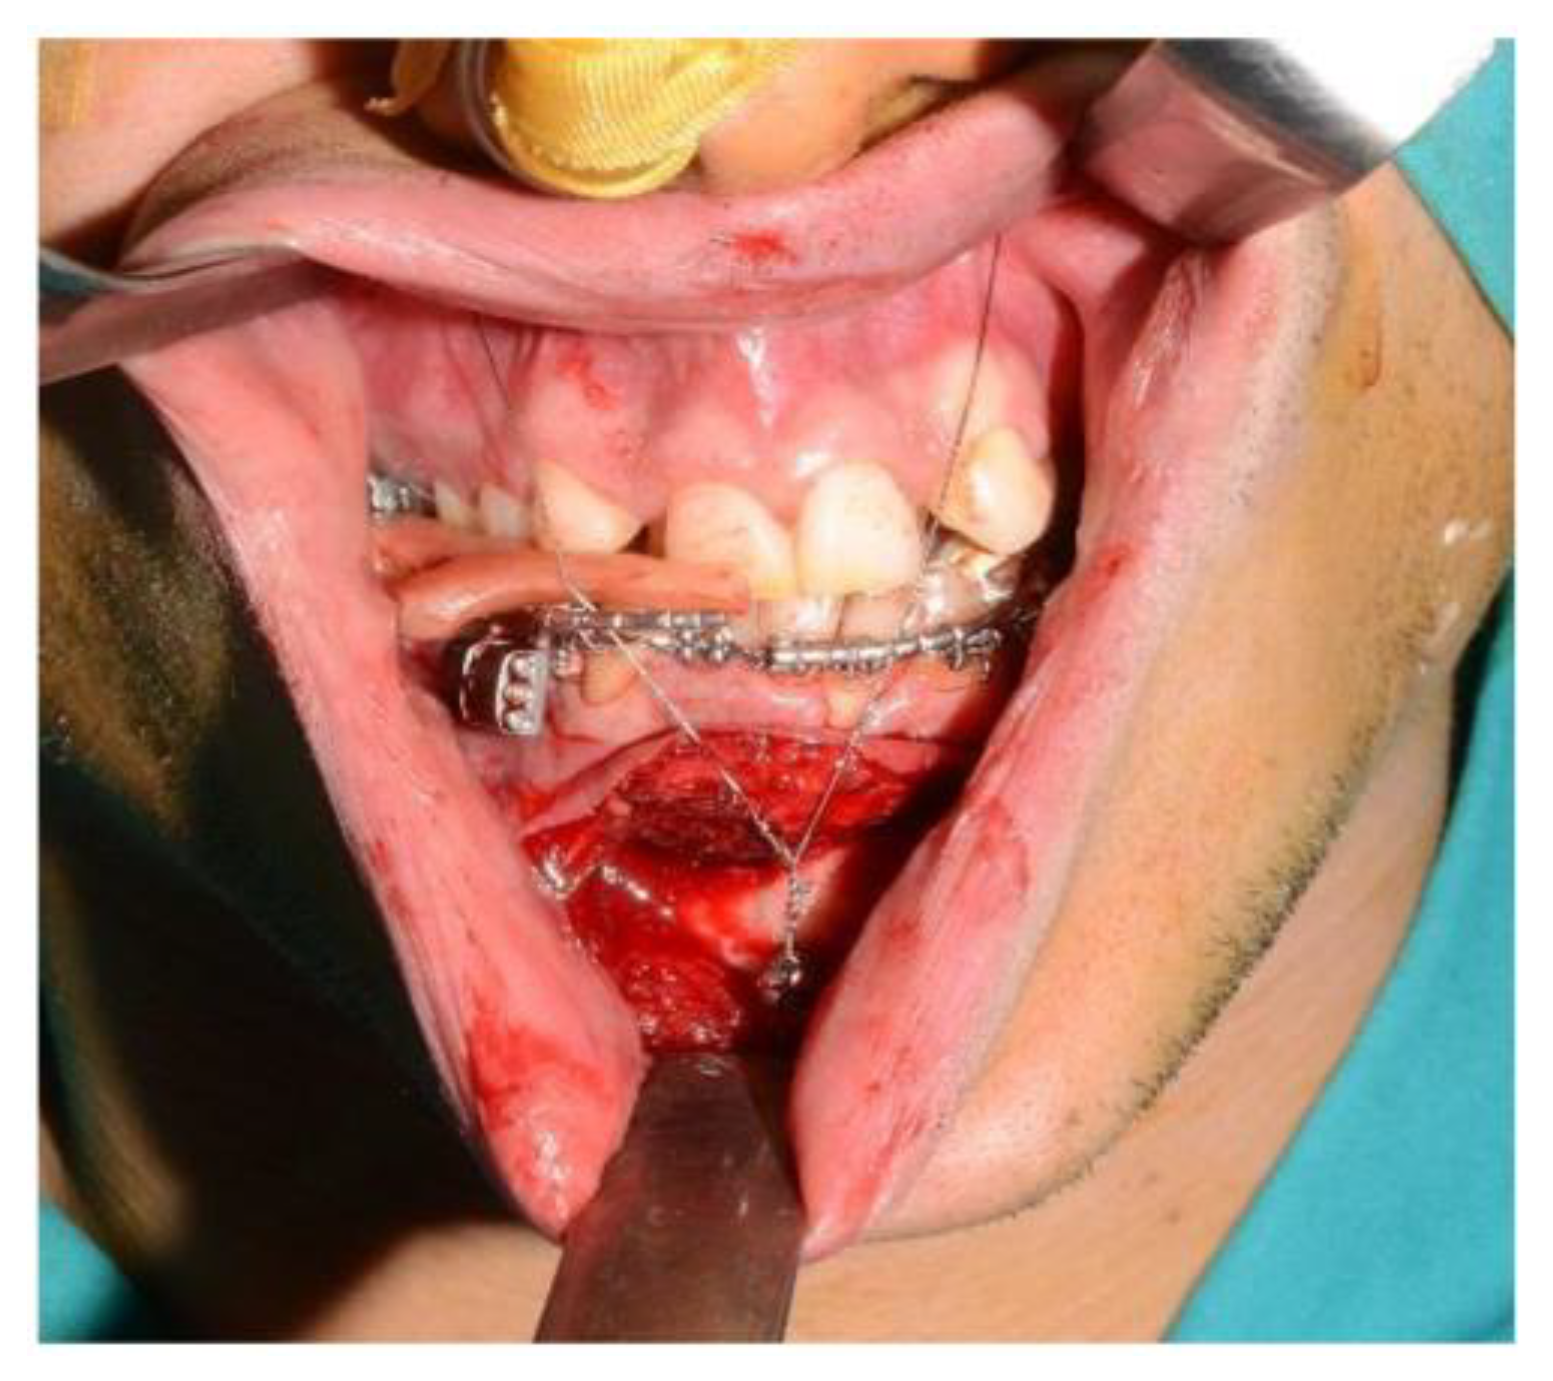

For the subapical osteotomy, it was decided to use the tracked tool technique with a piezoelectric scalpel to perform the procedure and avoid the risk of dental root injury, thereby enhancing surgical precision. A maxillary bite was created, and 5 screws with different space vectors were then placed on it, serving as fiducial markers. The bite was used to ensure that, during the entire surgical procedure, the mandible maintained the same position as in the preoperative CT scan. Virtual planning was performed with careful consideration of dental root preservation in the osteotomy tracing. During the surgical procedure, the Dynamic Reference Frame (DRF) was positioned in the left parietal bone, and the screws located on the bite were used as fiducial markers. The same bite used during the acquisition of CT scan images was used. Two screws were secured onto the maxillary bone, with an additional one in the mandibular symphyseal region. Simultaneously, an intermaxillary fixation was used to replicate as accurately as possible the mandible’s position maintained during the CT scan image acquisition (Figure 8).

The piezoelectric tool was registered by anchoring the three reflective spheres to the tool’s handpiece. At the same time, the tip of the piezoelectric device was marked and used as a reference for navigation (Figure 9).

The navigation accuracy was less than 1 mm. The subapical osteotomy was performed as previously planned (Figure 10).